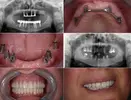

Implant tedavisi